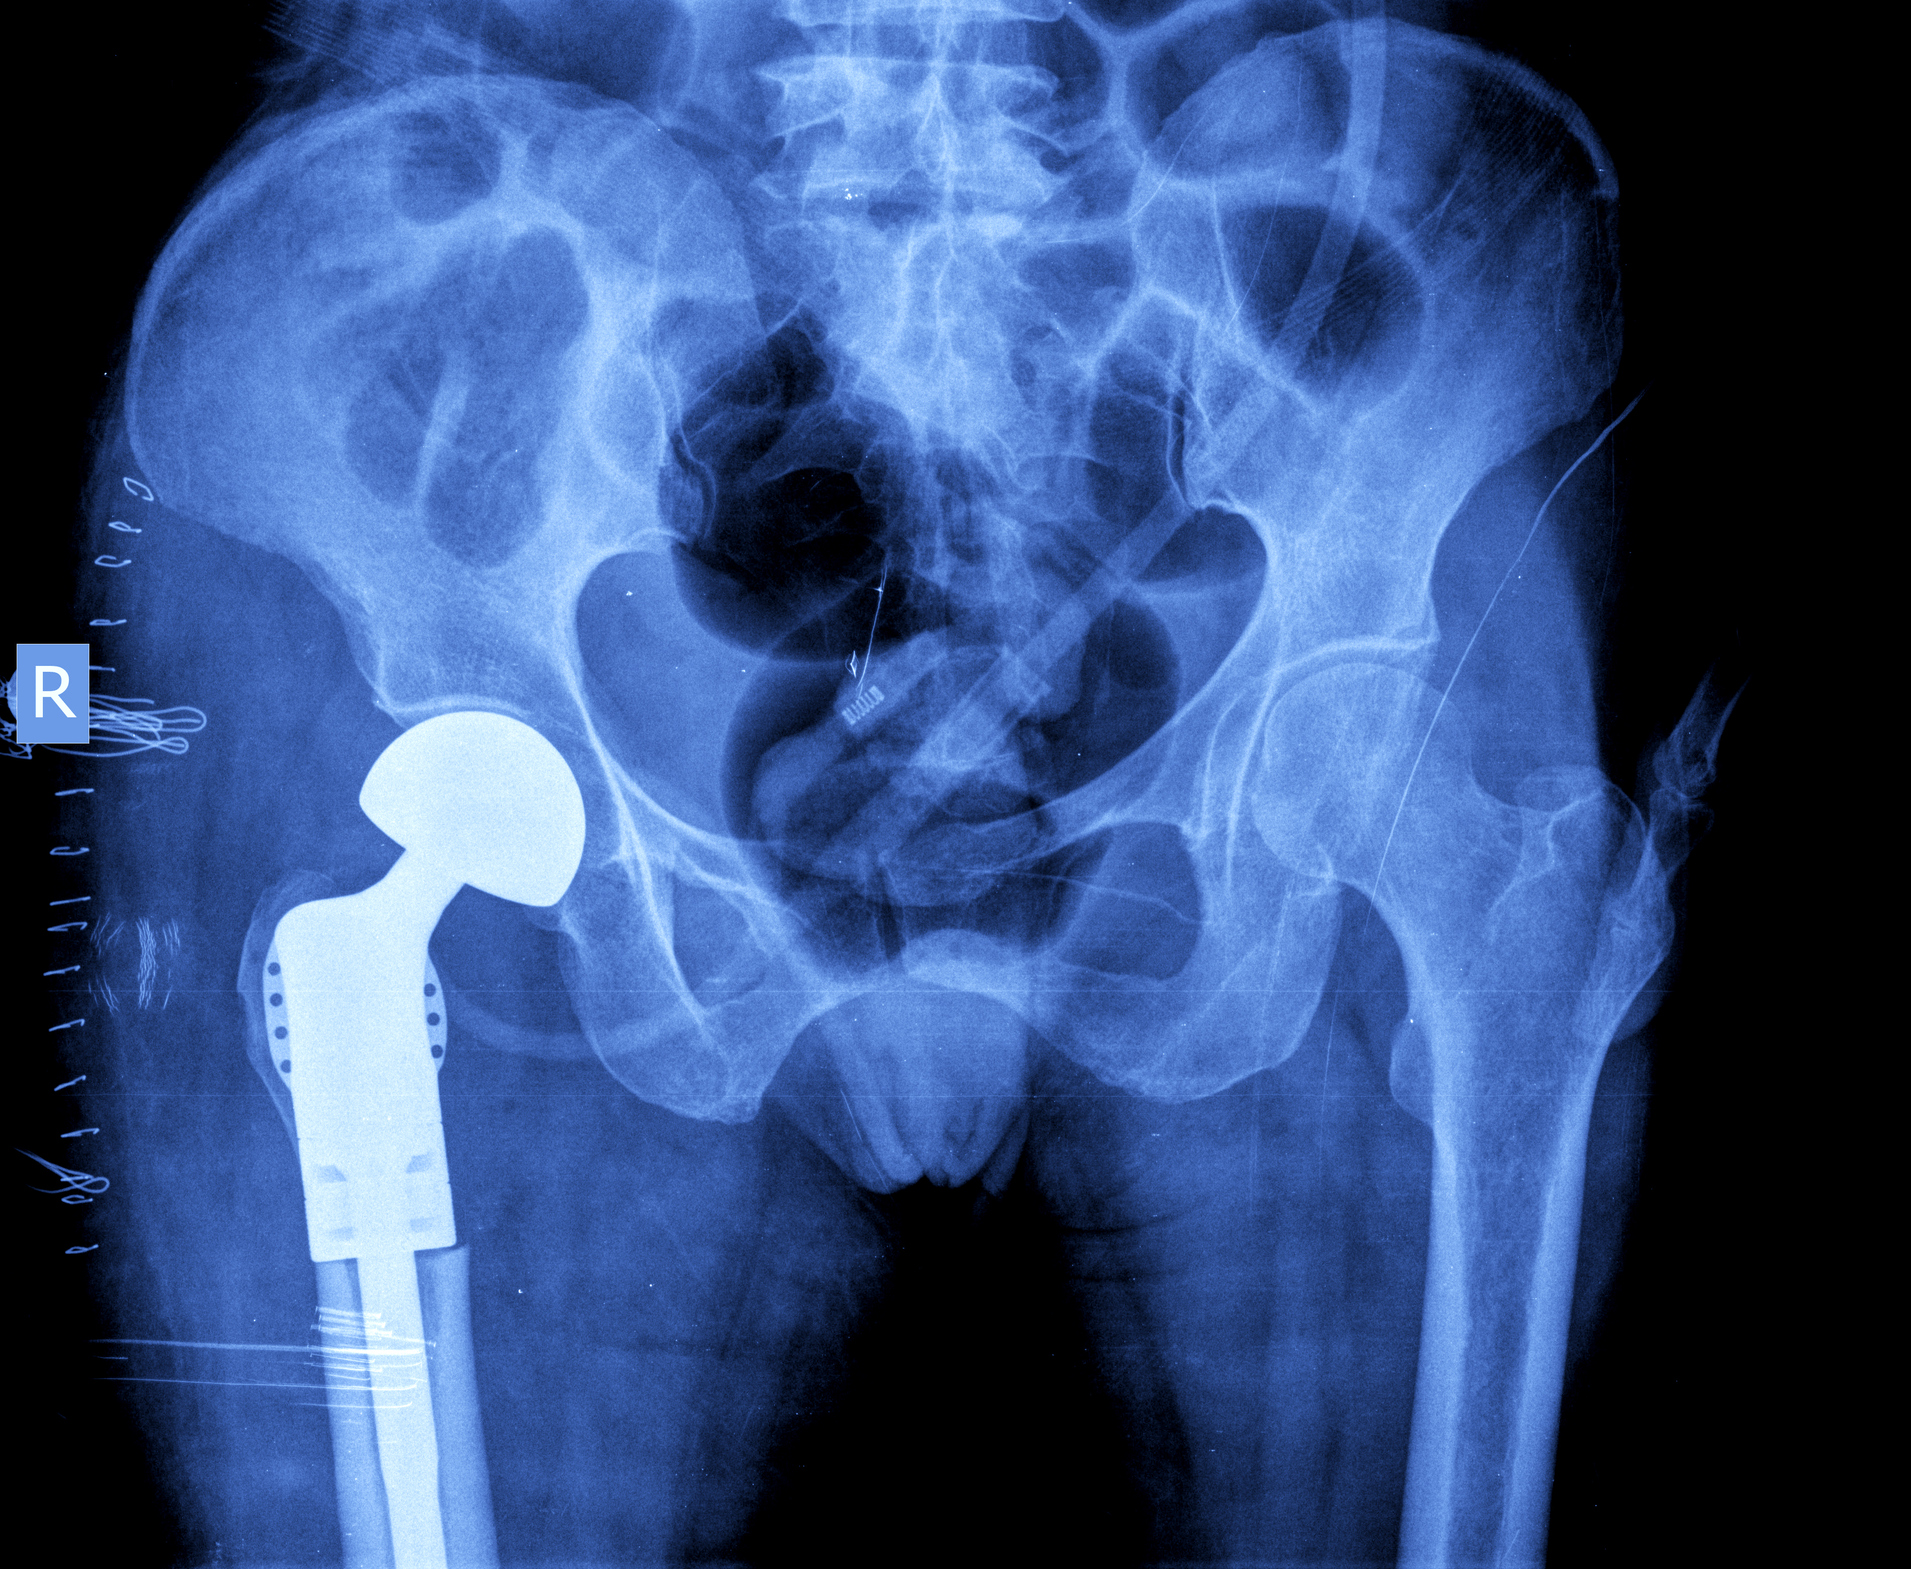

Туберкулез тазобедренного сустава рентгеновские снимки - фото презентация